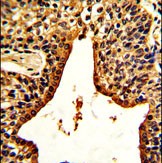

Product Image

- Formalin-fixed and paraffin-embedded human prostate carcinoma with VIP Antibody (C-term), which was peroxidase-conjugated to the secondary antibody, followed by DAB staining. This data demonstrates the use of this antibody for immunohistochemistry; clinical relevance has not been evaluated.